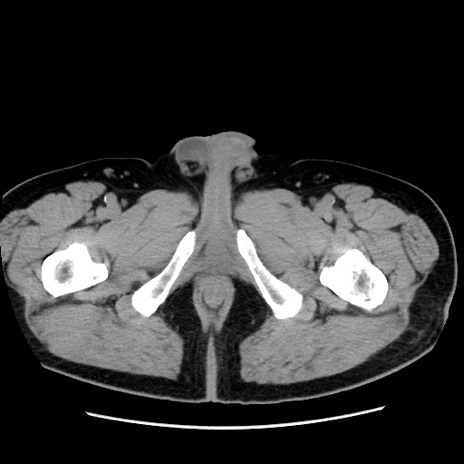

症例16(横断像)

【症例】 70歳代男性

【主訴】 腹痛、嘔吐

【現病歴】 約1ヶ月前より間欠的に腹痛と嘔吐あり、当院消化器内科を受診したところCTで多発する肝臓のLDAを指摘され、精査中であった。以降は消化器症状は安定していたが、2日前より嘔気と腹痛があり、同日より排便・排ガスが消失した。改善認めず、 本日、救急外来を受診した。

【既往歴】 大腸ポリープ切除後。

【身体所見】意識清明・会話良好、BT 36.3℃、BP 127/80mmHg、 P 80bpm、腹部:膨満あり、平坦・軟、上腹部正中および下腹部正中に圧痛あり、反跳痛なし、筋性防御なし。

【データ】WBC 7200、CRP 0.77